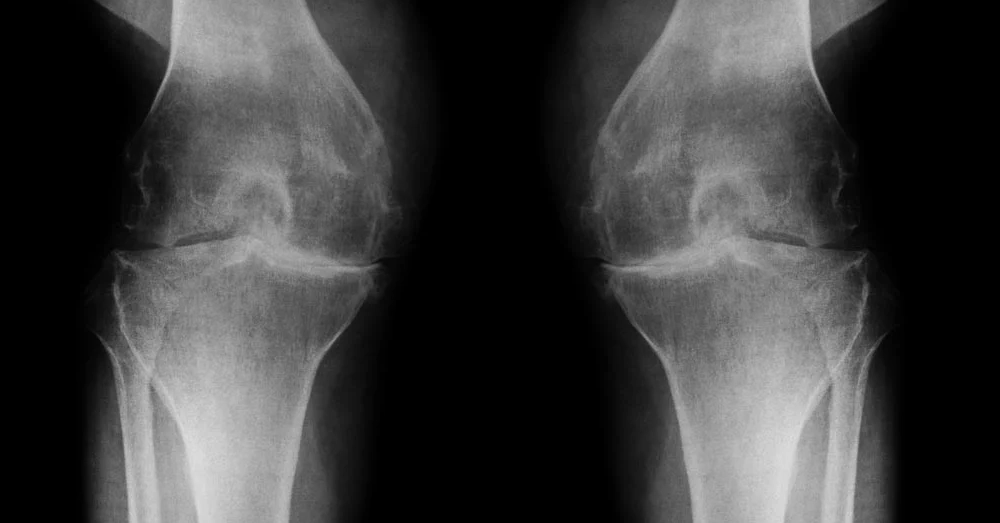

Osteoarthritis & joint degeneration (cartilage repair)

Chronic knee, hip, shoulder pain